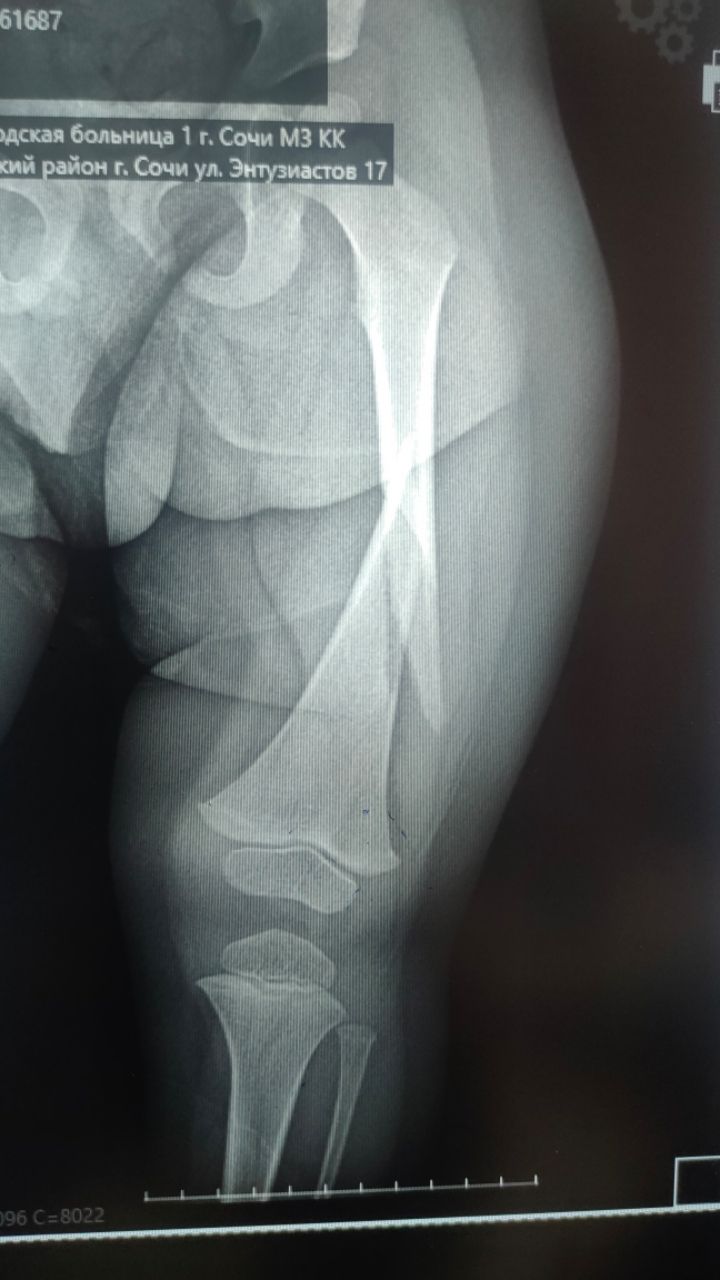

Тот день, роковой… когда ребенок просто шел к своим игрушкам и упал неудачно сломав бедренную кость разделила жизнь на до и после.

Была и больница и операция, и три недели прикованные к больничной койке на штыре...

Фото с больницы и снимка до операции и скелетного вытяжения и гипса и после